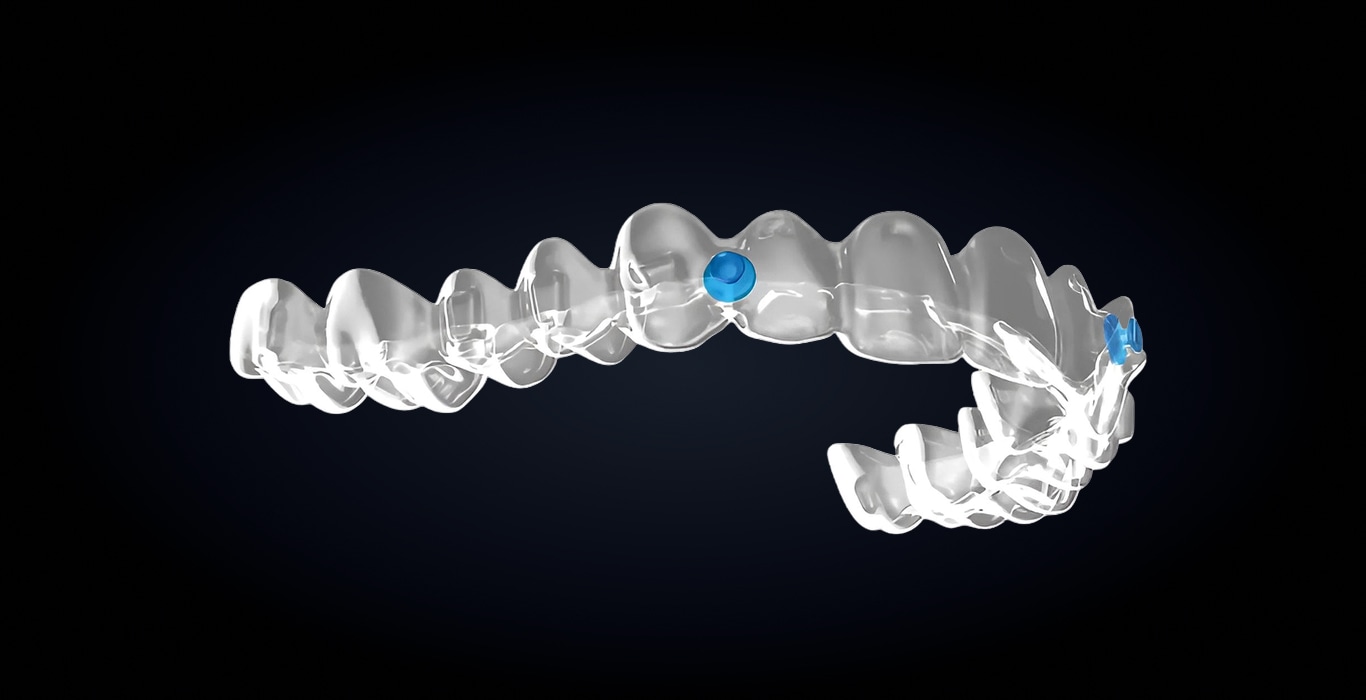

Обеспечивает дополнительную опору для работы с межчелюстными эластиками. Кнопка изготавливается как часть элайнера, что повышает его прочность и снижает риск деформации при использовании эластиков, а также сокращает время приема (не требует дополнительной установки).

Технология позволяет размещать эластические тяги в любой точке зубной дуги, а точное позиционирование с помощью AI-алгоритмов и биомеханической платформы masterForce⁴ обеспечивает надежное распределение усилий. Эргономичная форма снижает вероятность раздражения слизистой и повышает комфорт пациента, сохраняя прозрачность и высокую прочность.